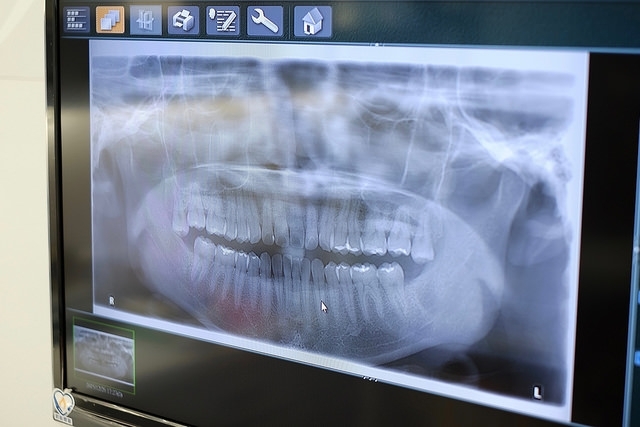

按慣例,初次看診一定都會拍攝全口X光片,醫師也會耐心說明牙齒的狀況,內人的牙齒非常健康也非常漂亮,就跟本人一樣。